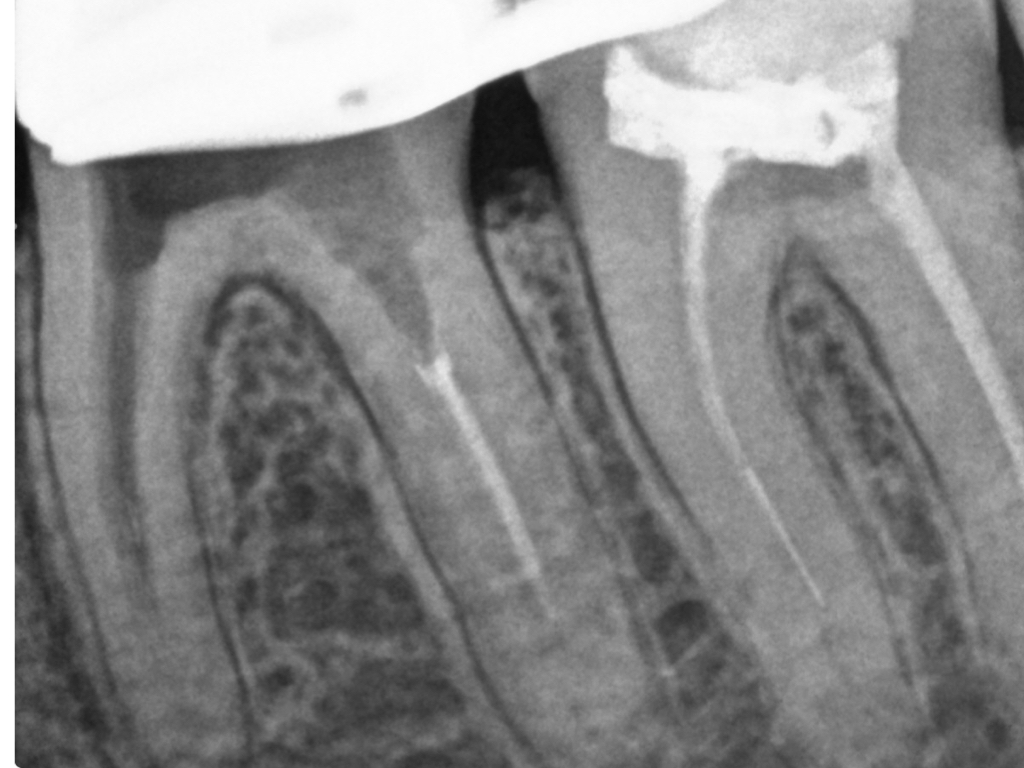

ws15102016-008

1024 × 768

4 auf einen Streich